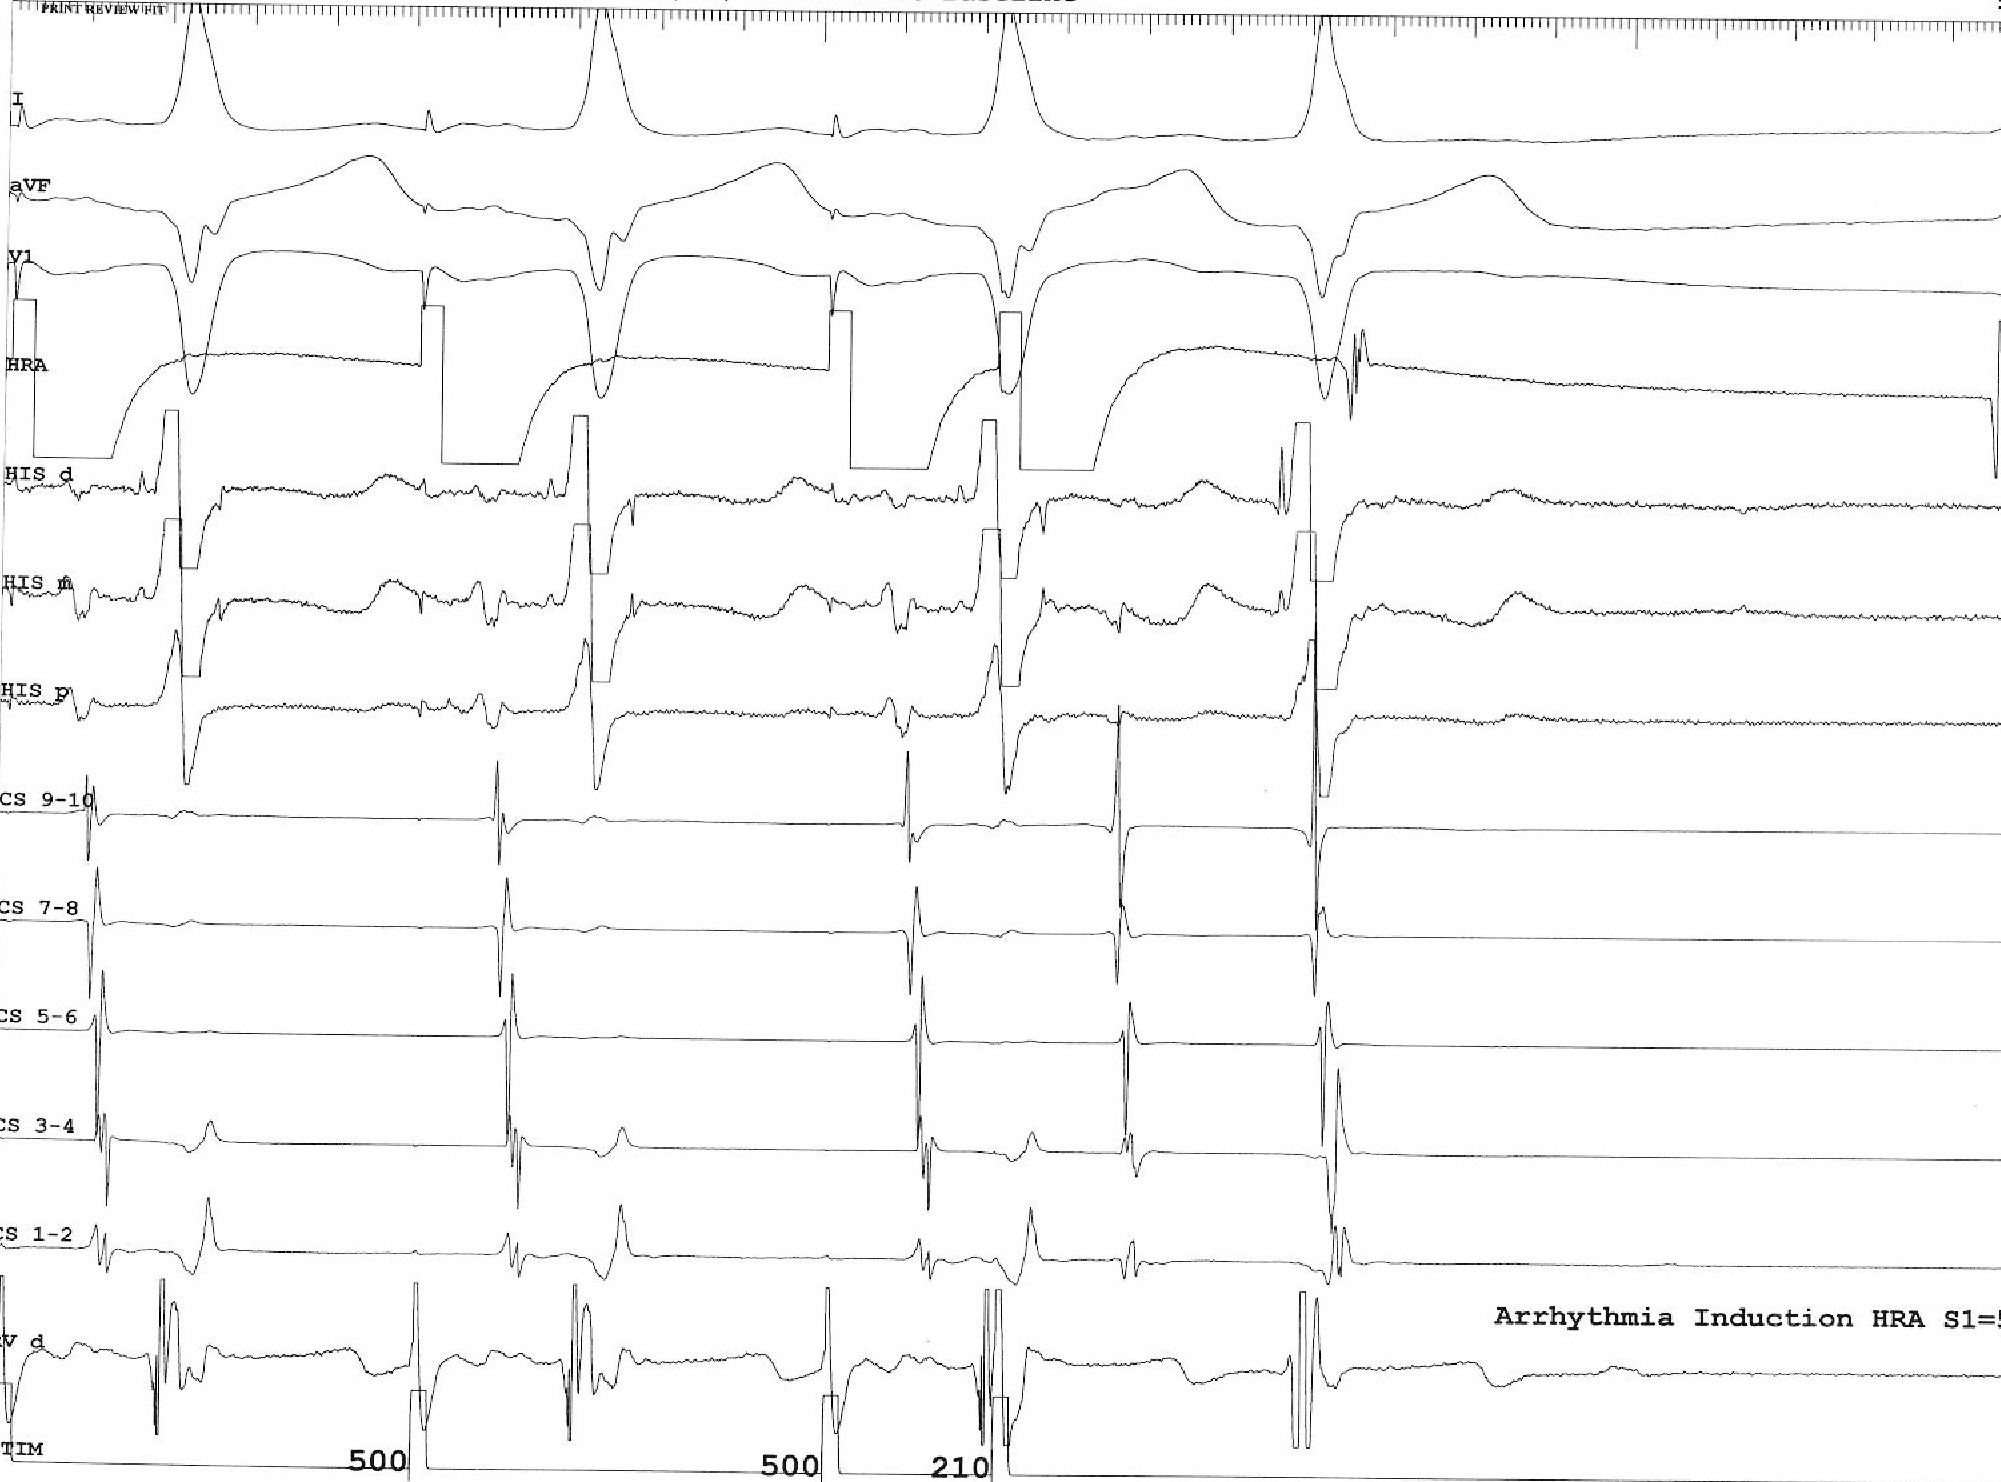

Tachycardia induction

• Chamber from which induced

• Induction dependent on critical AH prolongation

• Induction dependent on antegrade AP conduction block